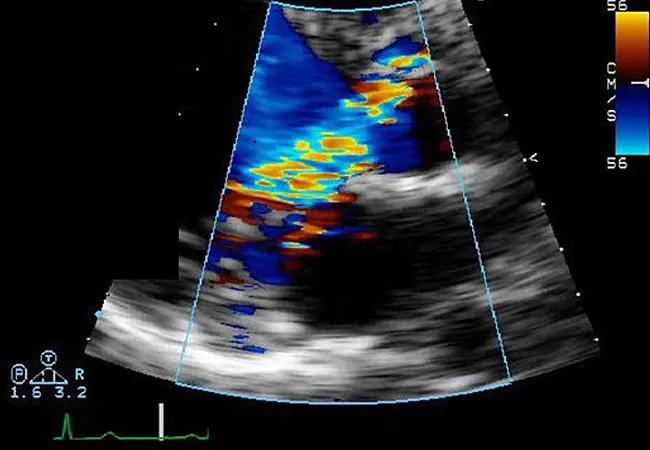

echocardiogram showing severe aortic regurgitation

Early Referral for Enlarged Roots Critical to Prevent Residual AR After Aortic Root Replacement With Valve Reimplantation

Residual AR related to severe preoperative AR increases risk of progression, need for reoperation